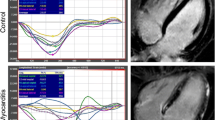

Myocardial strain analysis was performed using the CMR-FT method by the commercially available software Image Arena (2D CPA MR, version 4.6.4.40, TomTec Imaging Systems GmbH, Unterschleissheim, Germany). A detailed description of the methodology has been described our previous studies [22, 23]. Analyses were done in a random and blinded order regarding the patient clinical characteristics. Both the endocardial and epicardial contours were manually traced in long-axis (2, 3 and 4-chamber views) and short-axis images (basal, midventricular and apical levels) during end-diastole and end-systole. The manually traced contours were propagated throughout the images for the complete cardiac cycle. The global LV strains were automatically measured and calculated as the mean of the segmental strain values. Short-axis images were used to determine the global circumferential strain (GCS) and global radial strain (GRS), while long-axis ones (2, 3 and 4-chamber views) were used for the global longitudinal strain (GLS).

In contrast with the relatively extensive literature using echo-derived strain analysis, there are only two published articles using CMR-derived strain assessment in sarcoidosis patients. Dabir et al. [20] investigated 61 patients with biopsy-proven sarcoidosis using CMR-FT. GLS was significantly reduced in patients with sarcoidosis, even with an otherwise inconspicuous CMR, such that GLS may serve as a marker for early cardiac involvement. On the other hand, circumferential strain parameters were reduced only in patients with other CMR signs of cardiac sarcoidosis. In comparison to our study, there was a longer time since the diagnosis (≥ 10 years in 18% of patients) as well as a significantly higher percentage of LGE positive patients (70%) compared to our cohort (7%).

In the second manuscript, a different CMR technique, tagging imaging, was used for only circumferential strain analysis in 13 cardiac sarcoidosis patients [24]. Circumferential strain and strain rate were better in LGE negative segments than in LGE positive ones. No comparison with a control group was done, and neither any global strain analysis nor longitudinal data were described.